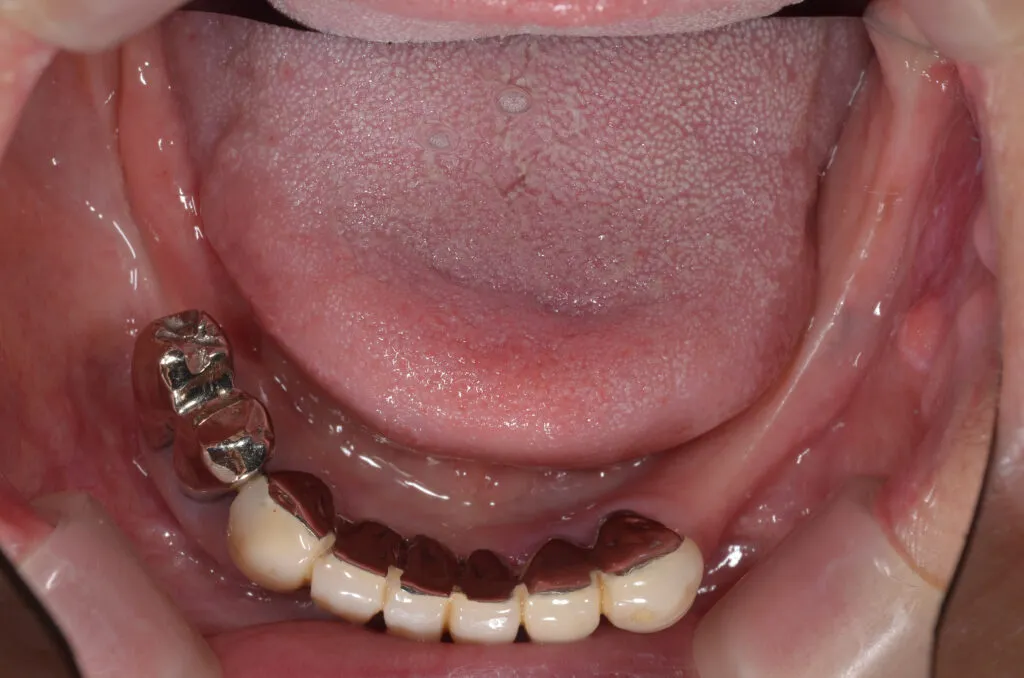

こちらの患者様の場合

【期間】2ヶ月

【費用】¥350,000~¥400,000/片顎(税抜)

【デメリット】精密に製作するため、保険の入れ歯よりも回数・費用がかかります。

上記写真は当院で上下総義歯を作製した患者さんです

上の写真は当院で上下総義歯を作製された患者さんです